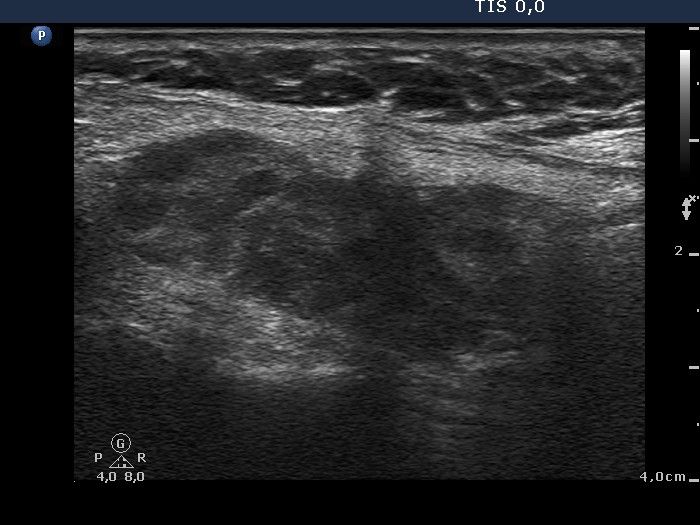

First examination (first and second rows of images):

Clinical data: A 62-year-old woman was operated on Graves' disease 15 years ago. She did not require replacement therapy. She was now referred for an evaluation of palpation and 7 kg weight loss and recurrent nodule described on ultrasonography.

Palpation: an operated thyroid without any abnormalities.

Result of blood test: hyperthyroidism (TSH undetectable, FT4 31.3 pM/L).

Ultrasonography. A diffusely hypoechogenic thyroid was found with small more hypoechogenic areas. The hypoechogenic area was surrounded with echonormal tissue. This pattern was interpreted falsely as a nodule by a previous examiner. The vascularization was average.

Cytology was performed from the right thyroid. Cytological diagnosis: benign pattern corresponding to hyperthyroidism.TSAb proved to be minimally elevated 2.4 U/mL (normal value below 1.5).

Thyrostatic therapy was started and the patient was treated with radioiodine 3 months later.

Comment. It is worth analyzing the ultrasound presentation - a large hypoechogenic area is surrounded with a thick echonormal rim. Although this pattern seems to be a nodule, it is one of the most characteristic appearances of a subtotally resected thyroid.